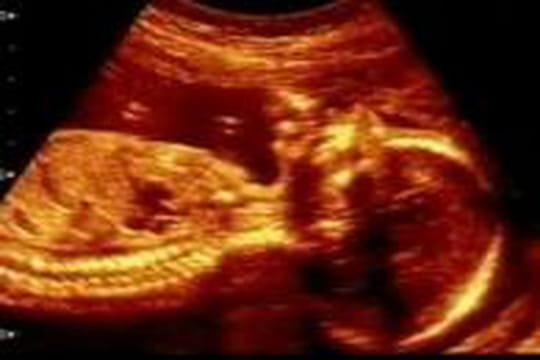

"Echographie de foetus"

"Pour la deuxième échographie, on était surtout très impatients et curieux de savoir si on attendait une fille ou un garçon. Cette révélation constituait pour nous un moment presque aussi attendu que la naissance ! Notre famille et nos amis trépignaient d'impatience. C'était un petit bonhomme. On nous l'a bien montré sur l'image mais j'ai dû repasser la vidéo (transmise sur K7 et ensuite numérisée) 4 fois à Alexis en faisant des arrêts sur image pour qu'il y voit plus clair... en vain."

"Lors de la deuxième écho, on cherche des ressemblances entre nous et le bébé" "Passé ce moment d'excitation, on nous a rappelé l'importance de cette échographie d'un point de vue médical. Notre bébé se développait bien : il n'y avait aucun problème. On distinguait avec précision tout le squelette, c'était incroyable. On a aussi vu et entendu son coeur battre. C'est extrêmement émouvant de se dire que c'est une chose qu'on ne verra qu'une seule fois dans sa vie. Dans un moment comme ça, on se tient la main très fort et on ne retient plus ses larmes."

" Les images assez nettes du bébé aident à se projeter dans l'avenir concrètement. On cherche des ressemblances. Son grand nez nous prouvait qu'on était bien ses parents ! Je crois que pour l'homme, cette échographie, plus que la première, permet de vraiment réaliser, de prendre conscience de la situation. Et pour la mère, de vivre le restant de la grossesse bien plus sereinement. Jusqu'à la naissance, j'ai visionné ces images plusieurs fois par plaisir mais aussi parce que ça m'aidait. Lors de la 3ème écho, on ne voit plus le bébé en entier, c'est donc moins impressionnant."